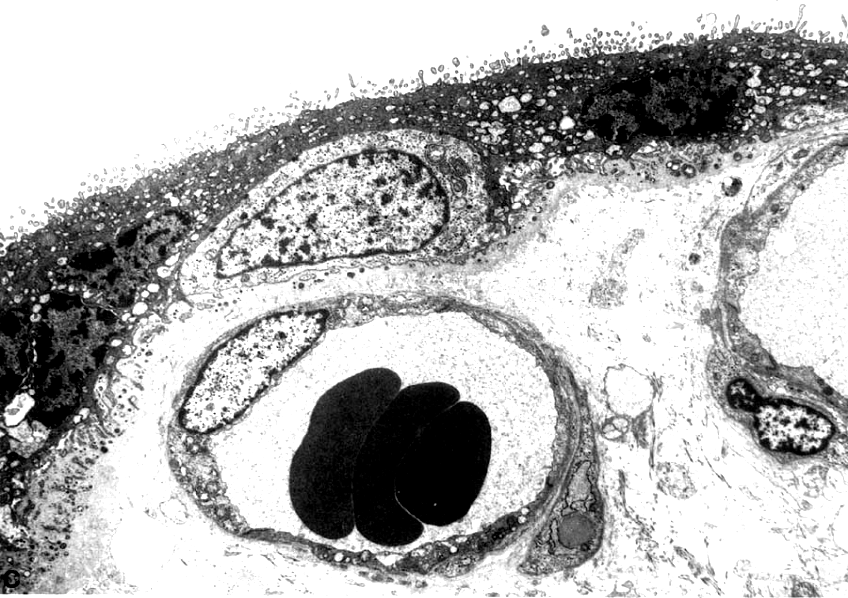

胎盘绒毛电镜图 (示胎盘屏障)

2.胎盘的血液循环和胎盘膜 胎盘内有母体和胎儿两套血液循环系统。母体动脉血从子宫螺旋动脉流入绒毛间隙,在此与绒毛内毛细血管的胎儿血进行物质交换后,再经子宫静脉,流回母体。胎儿静脉性质的血经脐动脉及其分支,流入绒毛毛细血管,与绒毛间隙内的母体血进行物质交换,从而成为动脉性质的血,后经脐静脉回流到胎儿。母体和胎儿的血液在各自的封闭管道内循环,互不相相混,但可进行物质交换。胎儿血与母体血在胎盘内进行物质交换所通过的结构,称胎盘膜(placentaI membrane)或胎盘屏障(placental barrier)。早期胎盘膜由合体滋养层、细胞滋养层和基膜、薄层绒毛结缔组织及毛细血管基膜和内皮组成。发育后期,由于细胞滋养层在许多部位消失,以及合体滋养层在一些部位仅为一薄层胞质,故胎盘膜变薄,胎血与母血间仅隔以绒毛毛细血管内皮和薄层合体滋养层及两者的基膜,更有利于物质交换。